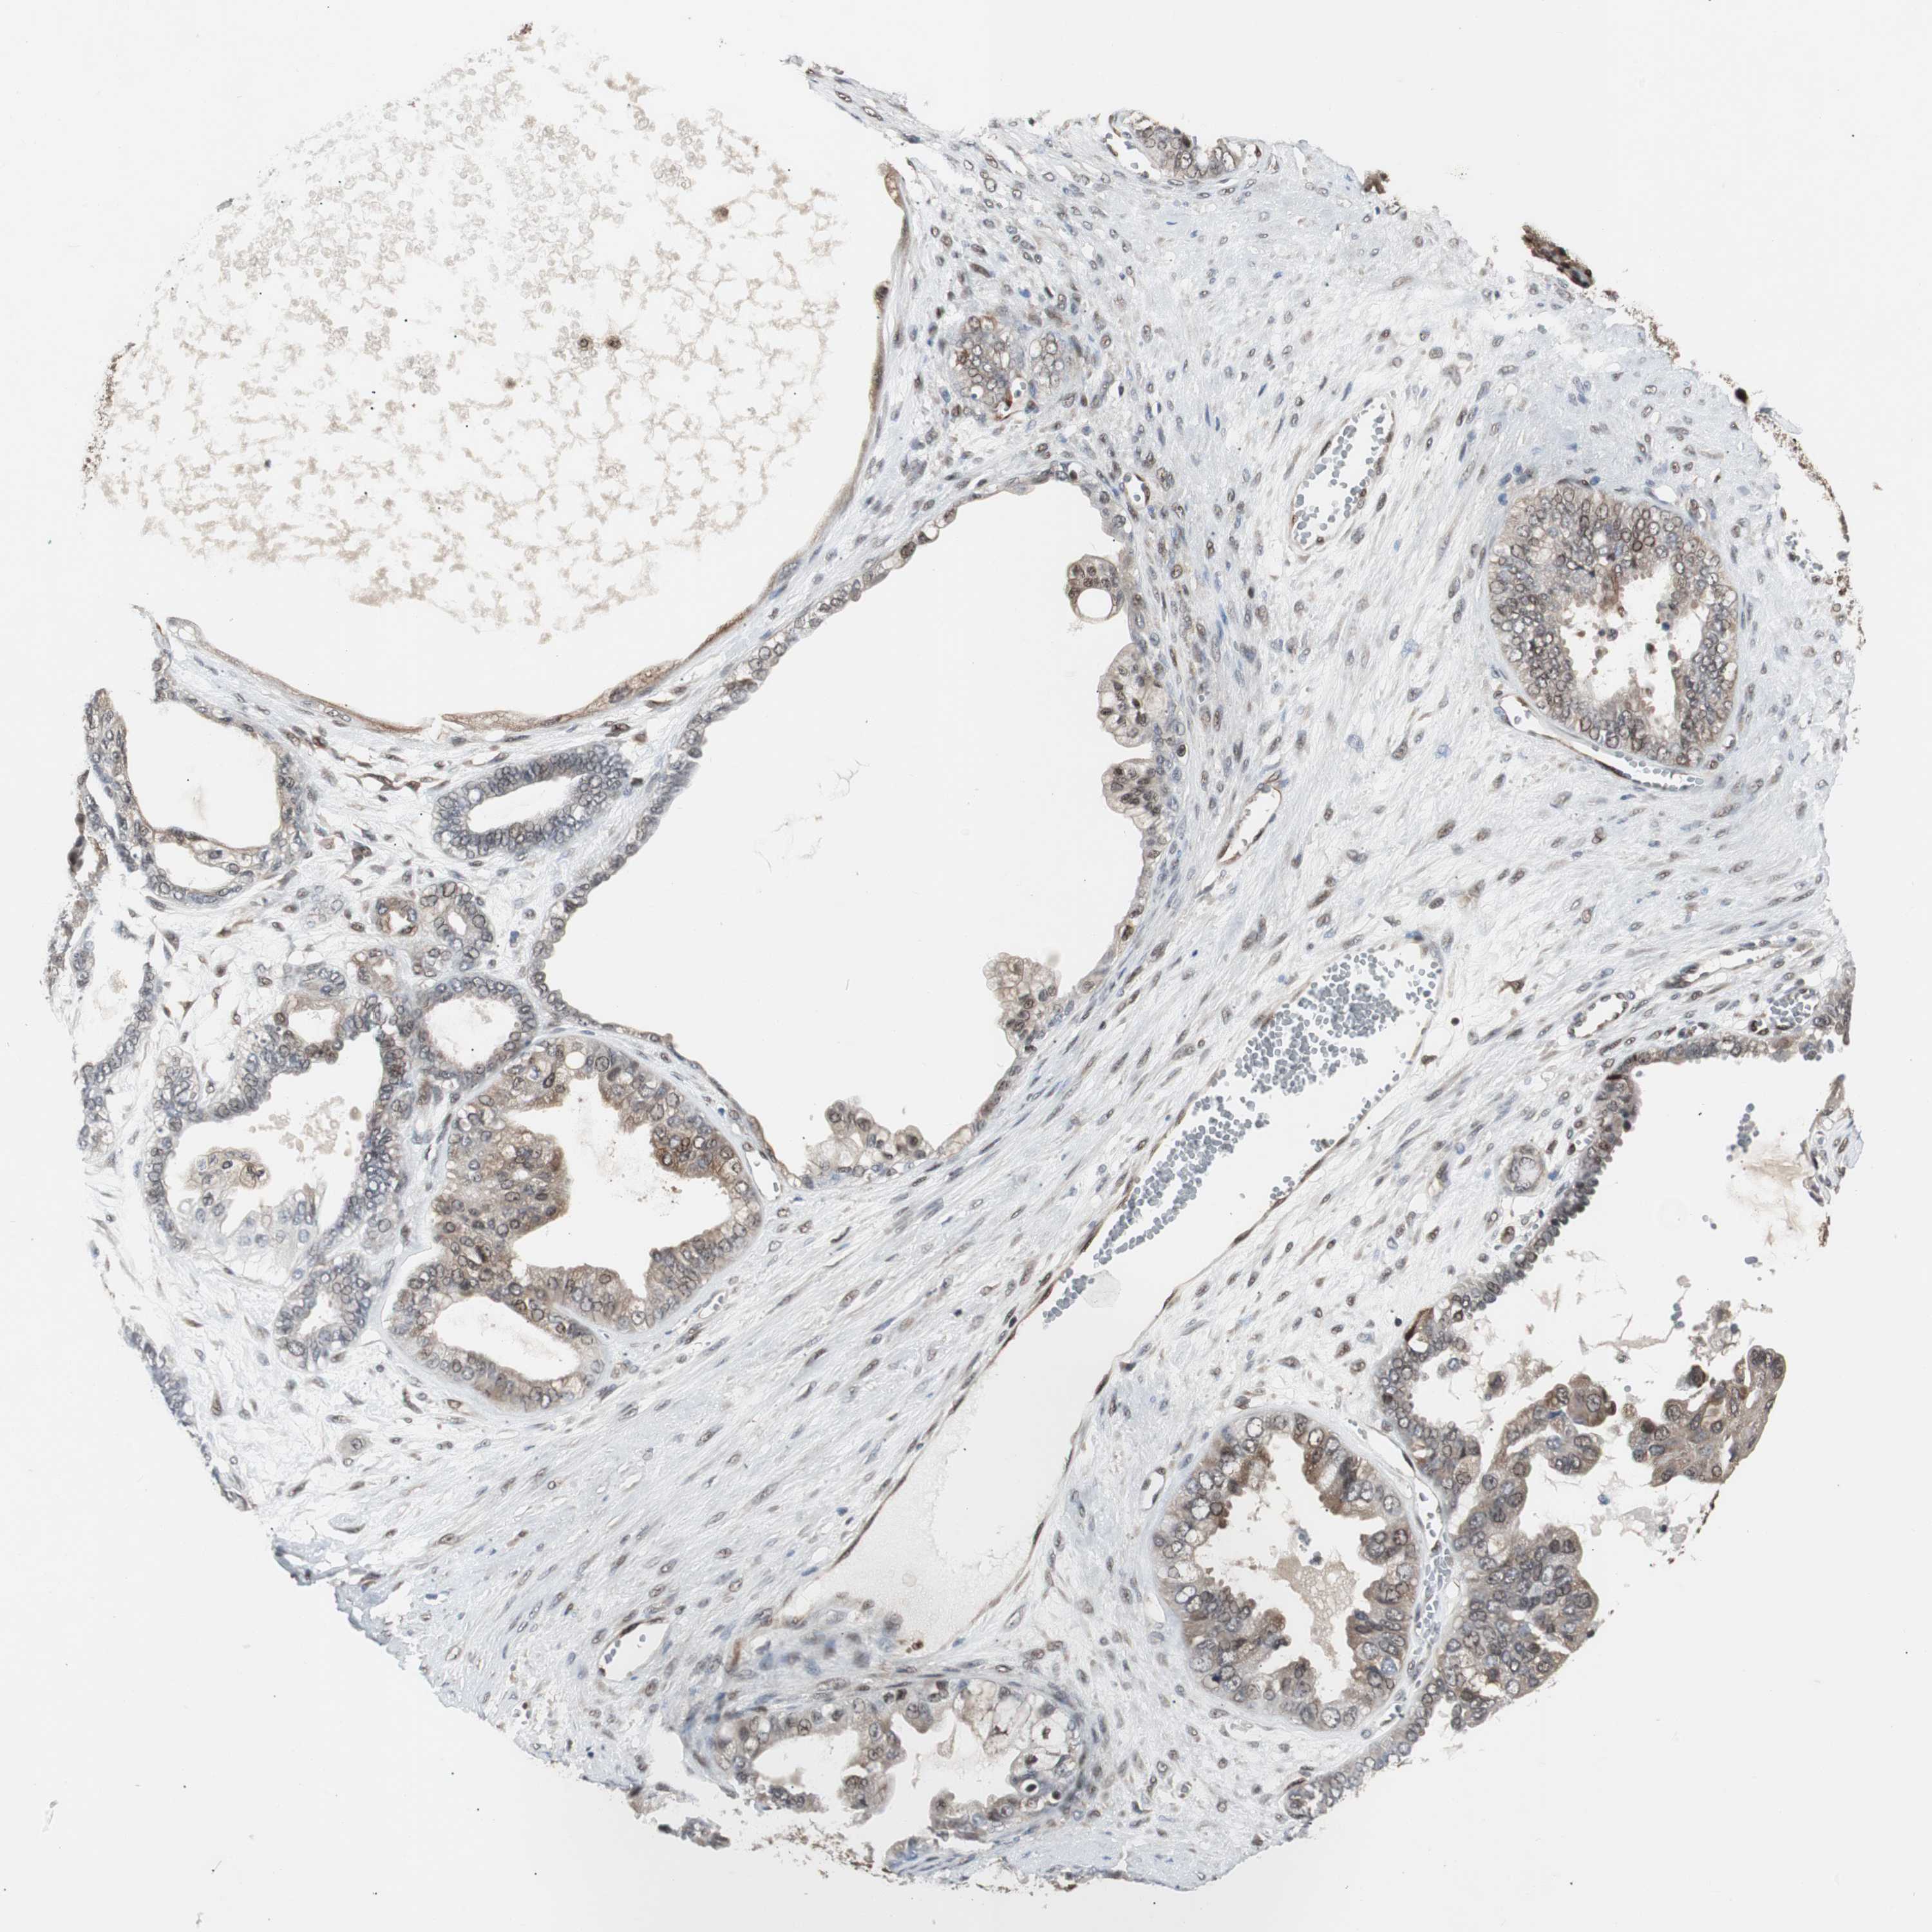

OVARIAN CANCER - Protein expressioni

A mouse-over function shows sample information and annotation data. Click on an image to view it in a full screen mode. Samples can be filtered based on level of antibody staining by selecting one or several of the following categories: high, medium, low and not detected. The assay and annotation is described here.

Note that samples used for immunohistochemistry by the Human Protein Atlas do not correspond to samples in the TCGA dataset.

Antibody stainingi

Antibody staining in the annotated cell types in the current human tissue is reported as not detected, low, medium, or high, based on conventional immunohistochemistry profiling in selected tissues. This score is based on the combination of the staining intensity and fraction of stained cells.

Each image is clickable and will lead to virtual microscopy that enables deeper exploration of all samples and also displays staining intensity scores, fraction scores and subcellular localization as well as patient and tissue information for each sample.

HPA022959

Carcinoma, NOS

Cystadenocarcinoma, serous, NOS